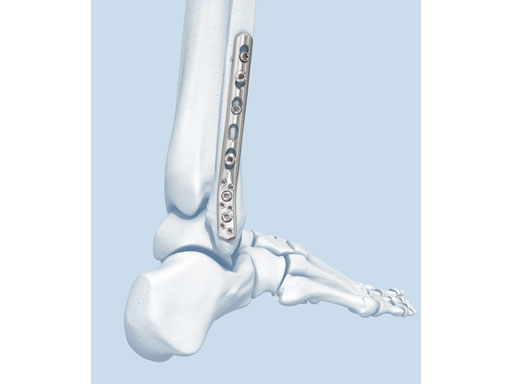

The LCP posterolateral distal fibula plate offers six round locking holes and two coaxial holes distally which accept 2.4 and 2.7 mm locking and cortex screws to provide multiple screw options. The distal holes are slightly divergent to help prevent screw pullout. The coaxial hole accepts both locking and cortex screws and its recess for screw heads minimizes screw-head prominence by allowing the screws to sit more flush with the plate, creating a low-profile construct. Its posterolateral position allows it to be placed deep to the peroneal muscles, minimizing the risk of wound healing problems due to prominence. A 2.7 mm lag screw may be placed through the distal screw cluster, and a syndesmotic screw may also be placed through the plate.

The anatomically precontoured plate shaft is only 2.25 mm thick yet substantially stronger than the one-third tubular plate. The combination holes in the shaft accept 3.5 mm locking screws, 3.5 mm cortex screws, and 4.0 mm cancellous bone screws.